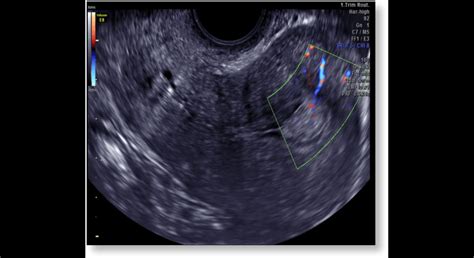

- Ultrazvukové vyšetrenie: Pomocou tohto vyšetrenia sa odhalí abnormálny typ maternice, a chýbanie plodu. Ultrazvukový obraz je známy odrazmi mnohopočetných priehradok moly pod názvom „snežná búrka“, ktoré na monitore naozaj vyzerajú ako husté sneženie. Typické pre toto ochorenie je tiež zobrazenie mnohopočetných luteinných cýst na vaječníkoch. V ultrazvukovom vyšetrení nenájdeme plod, ale obraz tzv. sneženia.